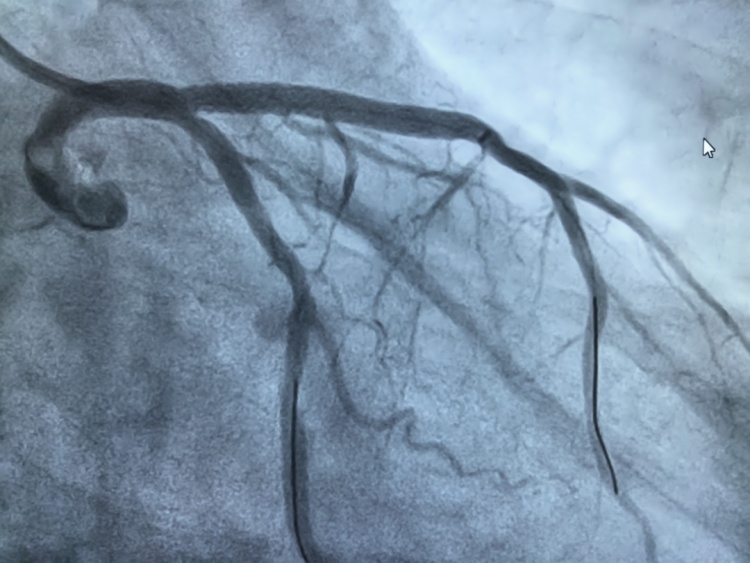

手术前

手术后